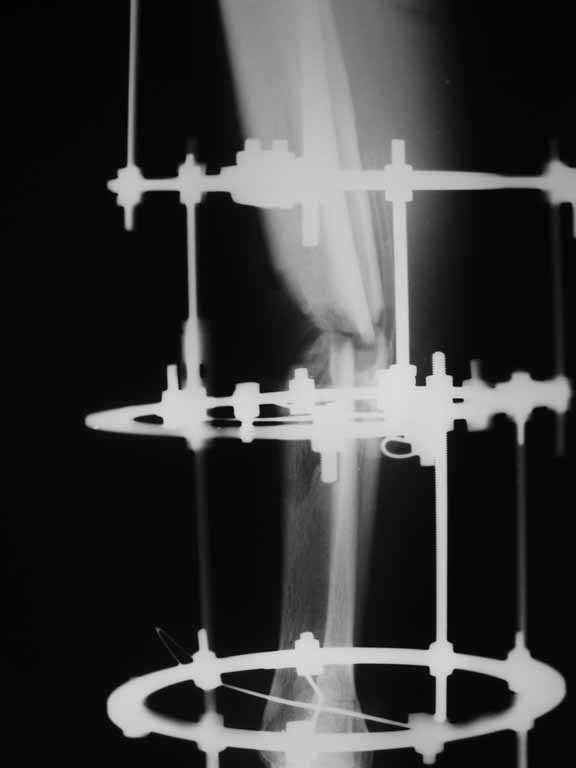

Re: Перелом большеберцовой кости с дефектом дифизарной части

Извините, не загрузились сразу все рентгенограммы.

Внедрение одного отломка в другой приведет к укорочению. Резекция с выращиванием резко удлинит срок лечения, вероятно, потребуются еще какие-то операции после завершения дистракции... А самое главное, это избыточные действия. Ведь дефект не сегментарный, краевой контакт есть.

Вполне достаточно закрытого интрамедуллярного остеосинтеза без открытых вмешательств в зоне стыка. Конечно, с рассверливанием. Если есть опасения насчет инфекции, то на гвоздь нанести цемент с ванкомицином.

Гвоздь тут будет эндопротезом диафиза на достаточное время для образования сращения в зоне имеющегося небольшого контакта. И далее страховкой от рефрактур.

Вот пример, тоже открытый перелом, первичный дефект, пробыл в аппарате 5 мес. Титановый гвоздь, сразу динамический, без покрытия. Больше не делали ничего.